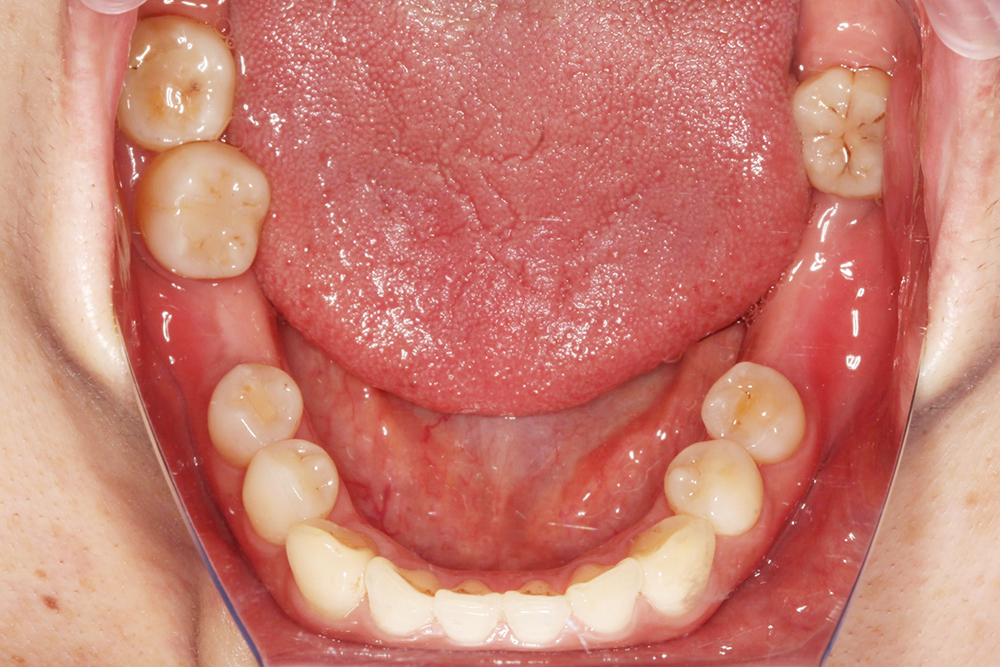

| 丹麥3shape口內掃描機 取代傳統印模方式,降低印模時的不適感,將口內缺齒情形以3D清楚呈現。 |

在術前規劃會使用數位化設計軟體,利用數位印模和數位排牙,精準地設計未來的牙齒排列和咬合狀態,更能真實模擬未來正式假牙效果,讓假牙設計既貼合個人需求,也更接近理想的美觀與舒適。

數位排牙可以預先模擬出手術後的效果,方便跟患者溝通,有任何想調整的地方也可以事先討論,讓整個過程更安心、更有把握。